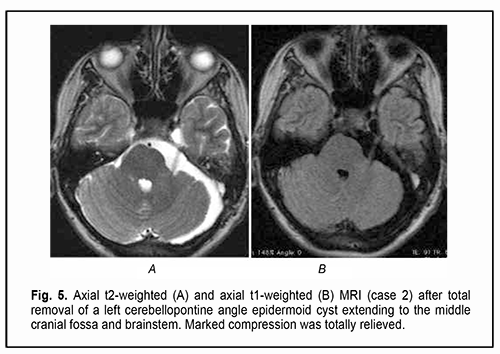

Of the 21 patients, 7 (33.33%) had a gross total removal and 2 (9.53%) had a near total removal of the cyst, with residual capsule fragments not exceeding 2-3 mm (Figs. 4, 5, 6, and 7). In addition, 12 (57.14%) had a subtotal removal of the cyst, with either intraoperative evidence of residual capsule fragments measuring from 2 mm to 10 mm, or postoperative MRI evidence of residual capsule fragments not exceeding 11 mm in the largest dimension. The capsule adhesion to surrounding neurocascular structure at the location where the dissection was difficult was seen in 18 patients (85.7%). In some cases, this can lead to the impossibility of safe total capsule dissection from the brainstem and cranial nerves. Postoperative follow-up ranged from 1 to 12 years, with mean and median values of 38.5 ± 4.8 months and 24 months, respectively (Fig. 8).

At presentation, ocular motor (OMA) were found in 4 patients (19.05%). Of these patients, 2 (9.52%) had isolated partial CN III (oculomotor nerve) palsy; one (4.76%), partial CN VI (abducens nerve) palsy; and one (4.76%), abnormalities affecting brain stem ocular motor structures (right and left gaze paresis). Patients with paralytic strabismus suffered from diplopia, dizziness, headache, nausea and instability of gait. In the two patients (9.52%) with isolated partial CN III palsy, there was compression of the optic nerve/chiasm complex, which was manifested by reduced visual acuity, descending optic atrophy and visual field defects (bitemporal heteronymous hemianopia with bitemporal paracentral scotoma in one patient and homonymous hemianopia with predominantly affected posterior chiasm in another patient). The isolated CN III lesion was manifested by the relevant ptosis, mydriasis, and restricted upward, downward and inward movements of the eye. The CN VI lesion was manifested by esotropia and a restricted outward movement of the eye. The isolated CN V (trigeminal nerve) lesion was found in 2 patients (9.52%) and accompanied by reduced corneal sensitivity and the development of neurotrophic keratitis. The CN VII (facial nerve) lesion was found in 2 patients (9.52%) and accompanied by lagophthalmos and the development of keratitis. It was dominating pain syndrome and trigeminal neuralgia, but not the initial presence of minor ophthalmological abnormalities that made 3 patients (14.28%) with involvement of several cranial nerves seeking medical care. Fundus examination revealed mild or moderate papilledema in three patients (14.28%). Of these patients, one had partial CN VI palsy and another had a brain stem associated ocular motor abnormality (OMA). Thirteen patients (61.9%; including the four who had had an OMA before surgery) had an OMA in the early postoperative period (days 5 to 7 after surgery): four had a CN III lesion (including the two in whom a CN III palsy appeared after surgery), five had a CN IV lesion, three had a CN VI lesion (including the two in whom a CN VI palsy appeared after surgery), and one had a brain stem nucleus abnormality. An OMA was present along with a CN V lesion in four patients (a lesion deteriorated to that of BNI-NS III in three of these four patients); along with a CN VI lesion in four patients (a CN VI palsy appeared in two of these four patients); and along with a lesion of CN IX and CN X in one patient. Both patients with preoperative compression of the optic nerve/chiasm complex showed recovery of visual acuity and visual fields due to decompression of the complex after surgery. Postoperatively, the papilledema regressed completely within a month in all the three patients with preoperative papilledema. In the late period (1-3 months) after surgery, CN III palsy was still present in 1 patient; CN IV palsy, in 4 patients; CN VI palsy, in 2 patients; and CN VII palsy, in 2 patients. Partial recovery of CN V function (with the development of keratitis and reduced corneal sensitivity) was observed in 4 patients, of whom 2 had had a preoperative CN V lesion, and the rest had postoperative dysfunction of CN V. The development of lagophthalmos and keratitis was assessed in the 4 patients with a CN VII lesion. Of these, the first patient was graded as HB II preoperatively and as HB IV postoperatively; the second, as HB I preoperatively and as HB II postoperatively; the third, as HB II preoperatively and as HB II postoperatively; and the fourth, as HB II preoperatively and as HB I postoperatively. Fourteen patients had no complications postoperatively. Of these, 6 had had a cranial nerve lesion before surgery. The period from the onset of ophthalmological dysfunction to surgery was 1 month for 5, 2 months for 1, 3 months for 2, 6 months for 1, 12 months for 1, 18 months for 1, 24 months for 1, 36 months for 1, and 72 months for 1 of the 14 patients. In 13 patients, ophthalmological functions were restored completely in the late postoperative period. The duration of ophthalmological and other neurological manifestations of the disease in patients with postoperative complications was 9 months for 1, 12 months for 2, 18 months for 1, 24 months for 2, and 180 months for 1 of the 7 patients. Of the three patients with no preoperative ophthalmological abnormalities, one patient had partial CN III palsy, and two patients, partial CN IV palsy, after surgery. All the three patients showed regression of both pain syndrome and trigeminal neuralgia. Of the nine patients who had undergone a total or near total tumor removal, 6 exhibited a complete recovery of ophthalmological functions. A partial tumor removal in a patient with a preoperative mild horizontal nystagmus also resulted in a complete recovery of ophthalmological functions. Of the 11 who had undergone a subtotal tumor removal, 5 exhibited a complete recovery of ophthalmological functions. The best surgery outcomes regarding recovery of ophthalmological functions were achieved in the patients with preoperative mild adhesion of the cyst capsule to cranial nerves who had undergone a total tumor removal. It is of note that 13 patients (61.9%) did not have symptoms of CN III, CN IV, CN V, CN VI, and/or CN VII lesions preoperatively, in spite of preoperative MRI and intraoperative evidence of the involvement of at least one of these nerves. Moderate-to-severe adhesions between the cyst capsule and nerve roots and/or brainstem were verified intraoperatively in 18/21 (85.7%) patients, and no adhesion was found in 3/21 (14.3%) patients. Table 2 demonstrates the frequency and severity of adhesions between the capsule of the epidermoid cyst and nerve roots and/or brainstem. There were 4 (22.2%) cases of severe adhesions and 1 (5.6%) case of mild adhesions for the epidermoids located at the midline of the floor of the fourth ventricle (Table 2). In addition, there were 8 (44.4%) cases of severe adhesions between the capsule of the epidermoid cyst and both nerve roots and brainstem, 4 (22.2%) cases of severe adhesions between the capsule and nerve roots only, and 1 (5.6%) case of severe adhesions between the capsule and CN only for the epidermoids located at the brainstem. The three patients with no capsule adhesion had a complete neurological and ophthalmological recovery in the late postoperative period.